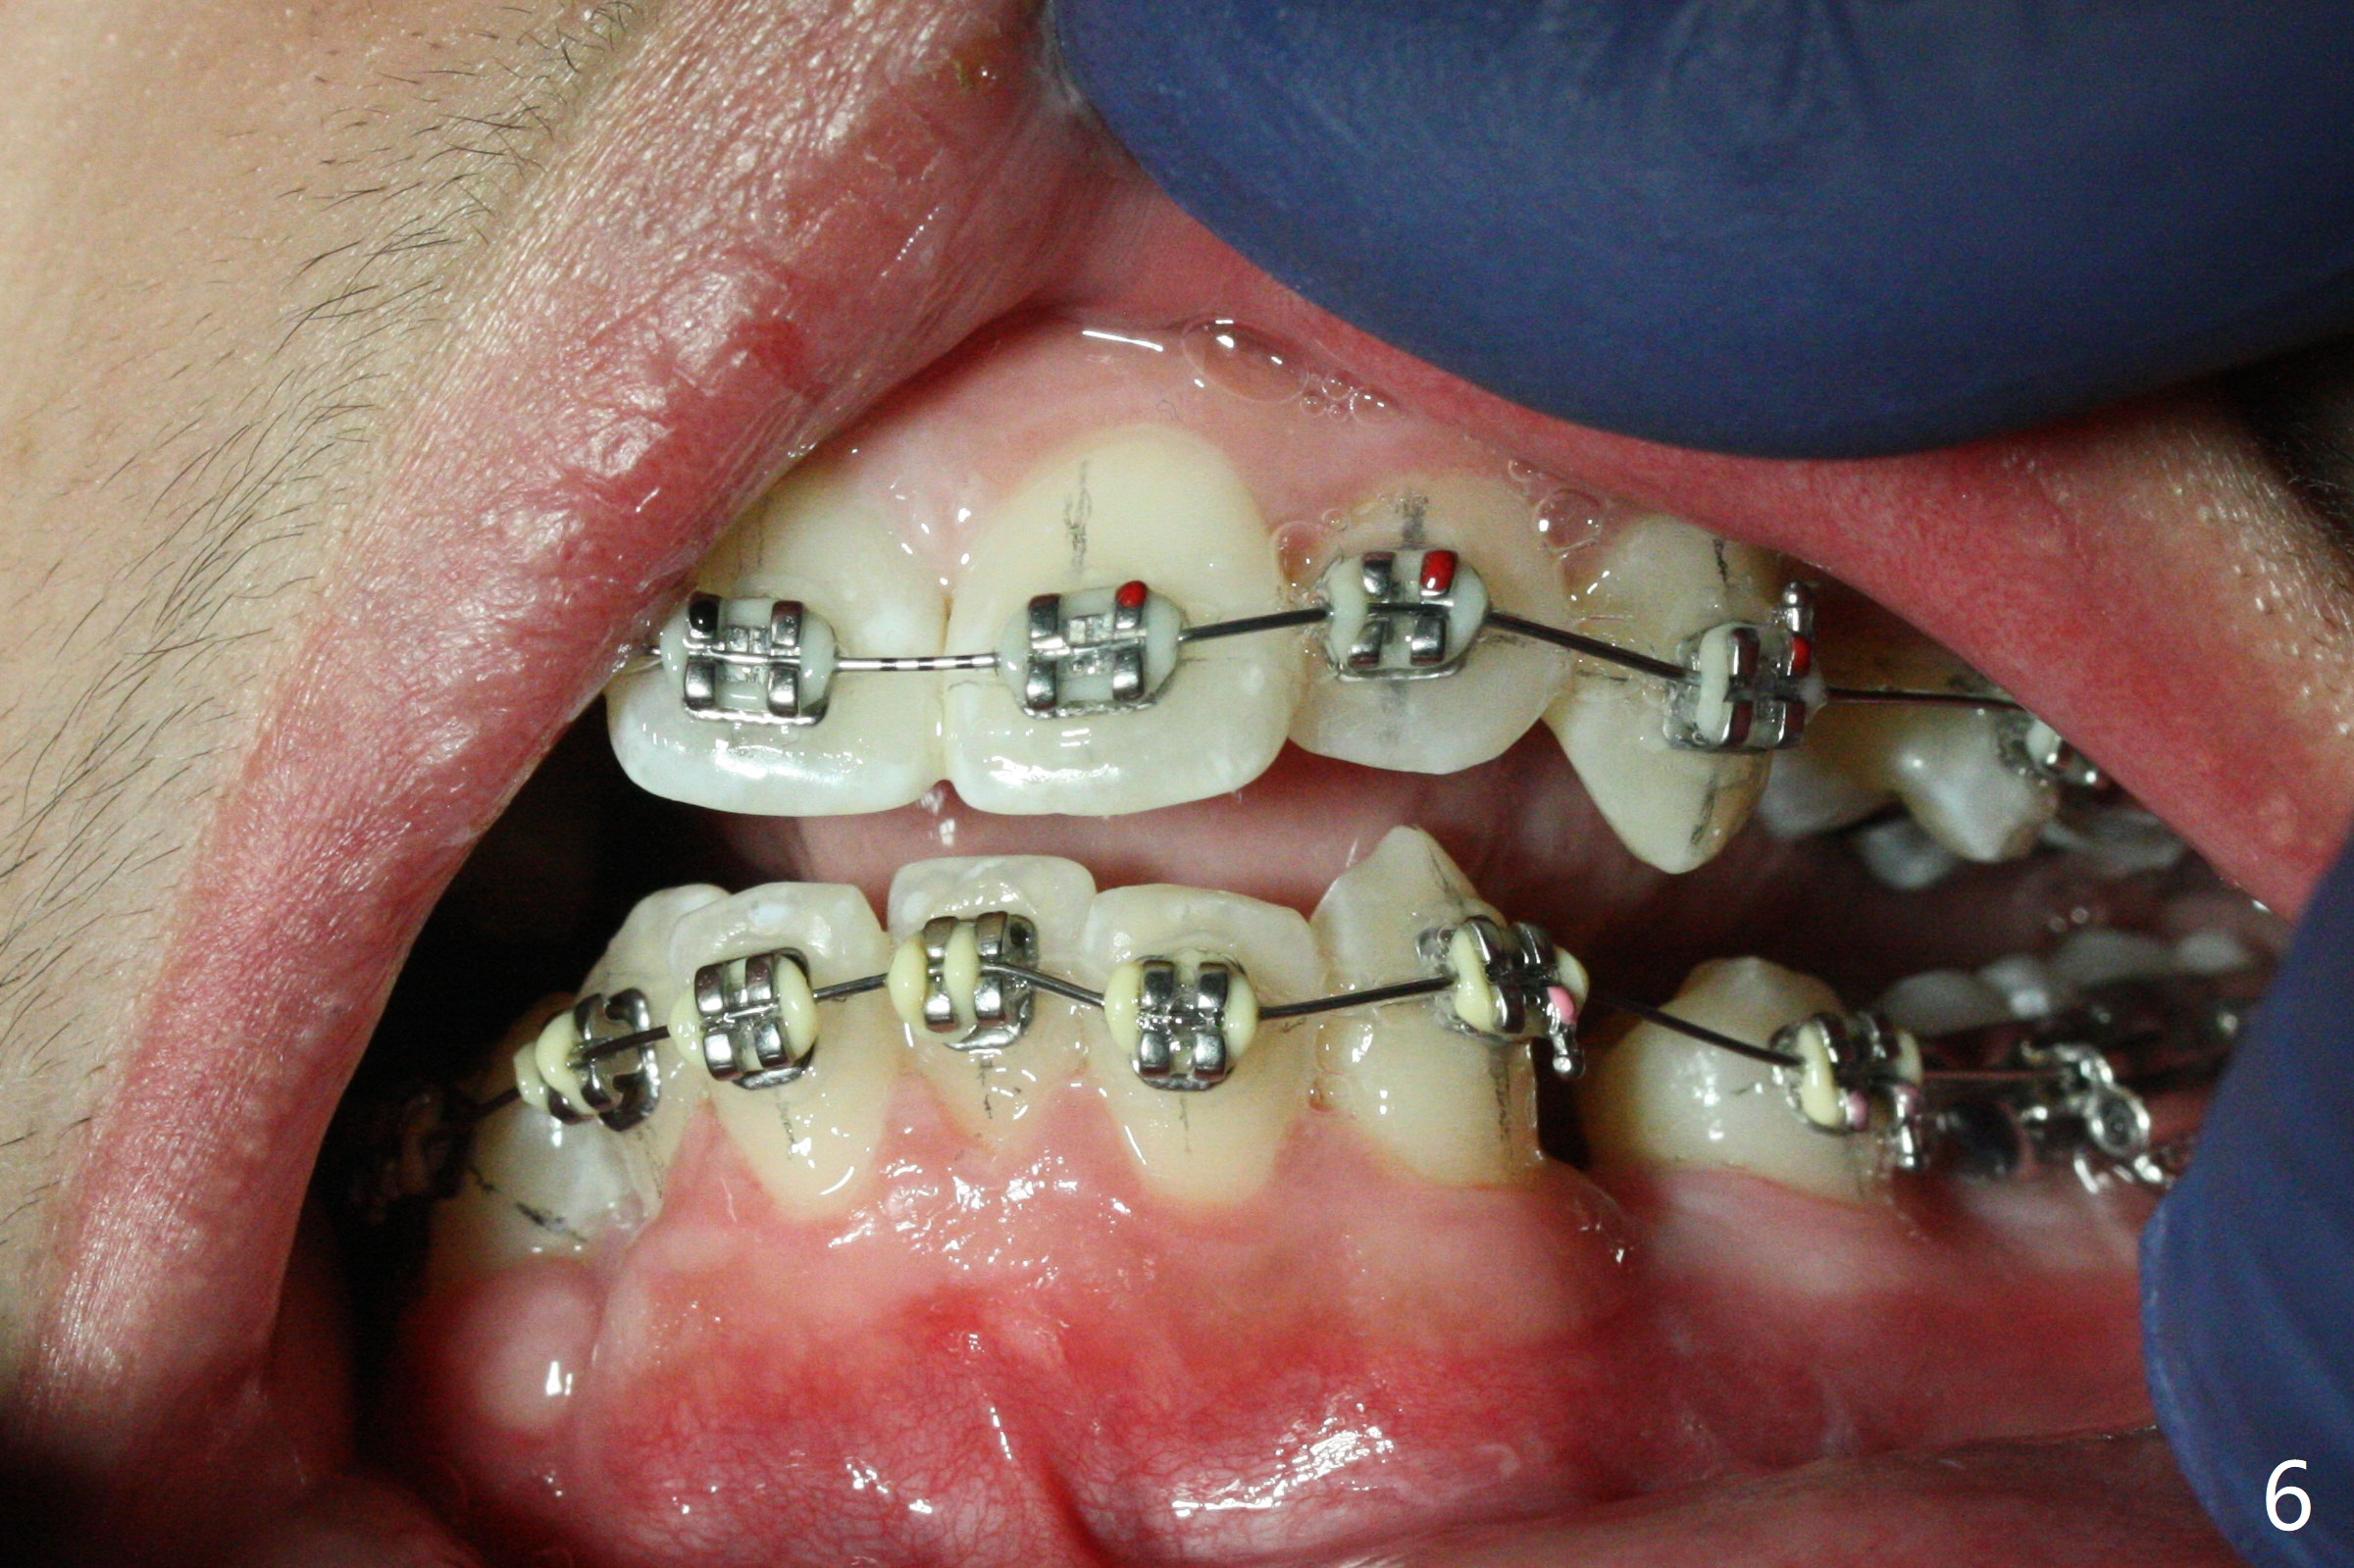

The socket of LR3 heals 2 months post extraction (Fig.4: *). LR4 is bracketed as LR3. Brackets and Bands are placed with 14 niti wires (Fig.5,6).